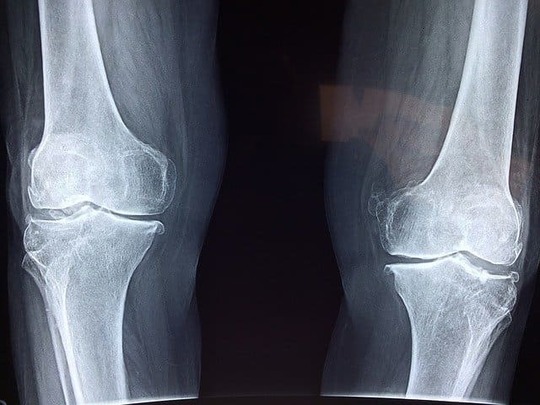

ブシャール結節は、指の変形性関節症のひとつ

ブシャール結節は、指の変形性関節症のひとつです。指の第二関節の軟骨が摩耗することによって、関節の変形、腫れ、屈曲などが起こります。中には痛みを全く感じない人もいます。